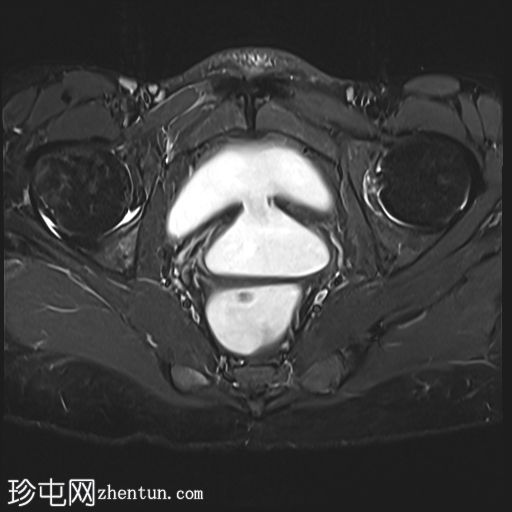

膀胱充盈前

MRI

膀胱后壁与阴道前壁之间存在宽阔的瘘管。膀胱内可见气液平面。

膀胱充盈前,该影像无法显示阴道后穹窿上缘与直肠中段前壁之间较小的瘘管。